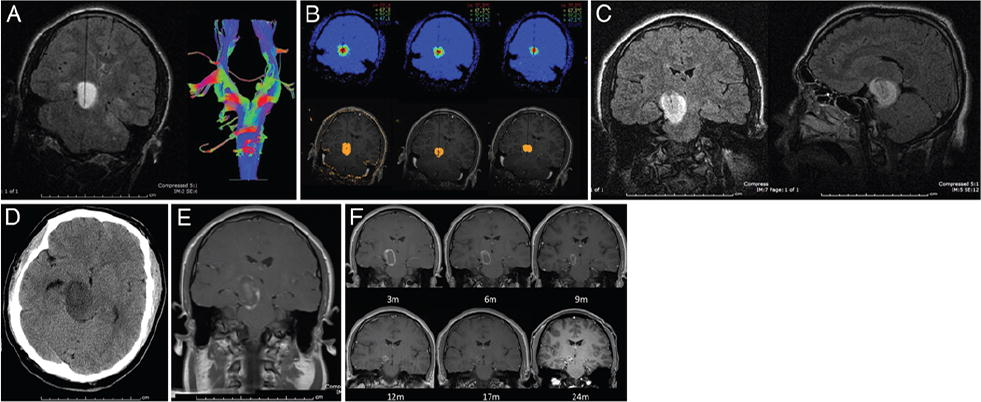

较初用MRgLITT治疗患有1型神经纤维瘤病(NF1)和有症状的右中脑-丘脑毛细胞星形细胞瘤的16岁男孩。这是该系列中出现临床消融后水肿的病例。术前的影像学检查显示纤维被肿瘤移位(图A)。通过叠加处理将激光纤维缩回冷却导管内来实现消融,并且热图显示了估计的较终损伤(图B)。在消融当天获得术后FLAIR MR图像以显示治疗区(图C))。患者正在经历术后嗜睡和左侧无力,消融后未做对比检查的CT显示明显水肿(图D)。手术后一周,T1加权对比增强MRI显示消融区域的对比增强环和水肿的程度的消退(图E)。增强边缘随时间逐渐减小(图F)。

A : Preablation冠状T2加权和表示示踪图像激光在16岁的患者与NF1放置和示踪和不断增长的对症右中脑/丘脑毛细胞型与从头LITT治疗星形细胞瘤。B: LITT增加的消融和较终损伤评估。C:消融后的冠状和矢状T2加权FLAIR MR图像显示了消融区和局限性水肿。D:消融后进行的非对比CT扫描显示出明显的水肿。E:消融后1周的Gd后T1加权MR图像显示了消融环对比增强和程度的浮肿。F: 消融后3、6、9、12、17和24个月获得的冠状动脉T1加权对比增强MR图像显示肿瘤体积减小。